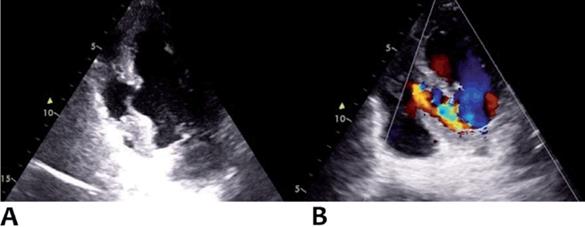

Evoluciona en las horas posteriores con tendencia a hipotensión y edema pulmonar. Se realizó ecocardiograma transtorácico (ETT) a las 18 horas del procedimiento (figura 3) que mostró: ventrículo izquierdo con aquinesia y franco afinamiento de los segmentos inferior medio-basal e ínfero-septal basal, con hipercontractilidad de los segmentos medio-apicales. Fracción de eyección del ventrículo izquierdo estimada en 55%. Presenta sobre la pared ínfero-septal (transición de segmento basal y medio) comunicación interventricular (CIV) de 23 mm de diámetro, anfractuosa. Válvula mitral con insuficiencia leve.

Figura 3: A) Ecocardiograma transtorácico con enfoque apical modificado que muestra rotura septal a nivel medio basal. B) Imagen en Doppler color con evidencia de pasaje de flujo hacia el ventrículo derecho.